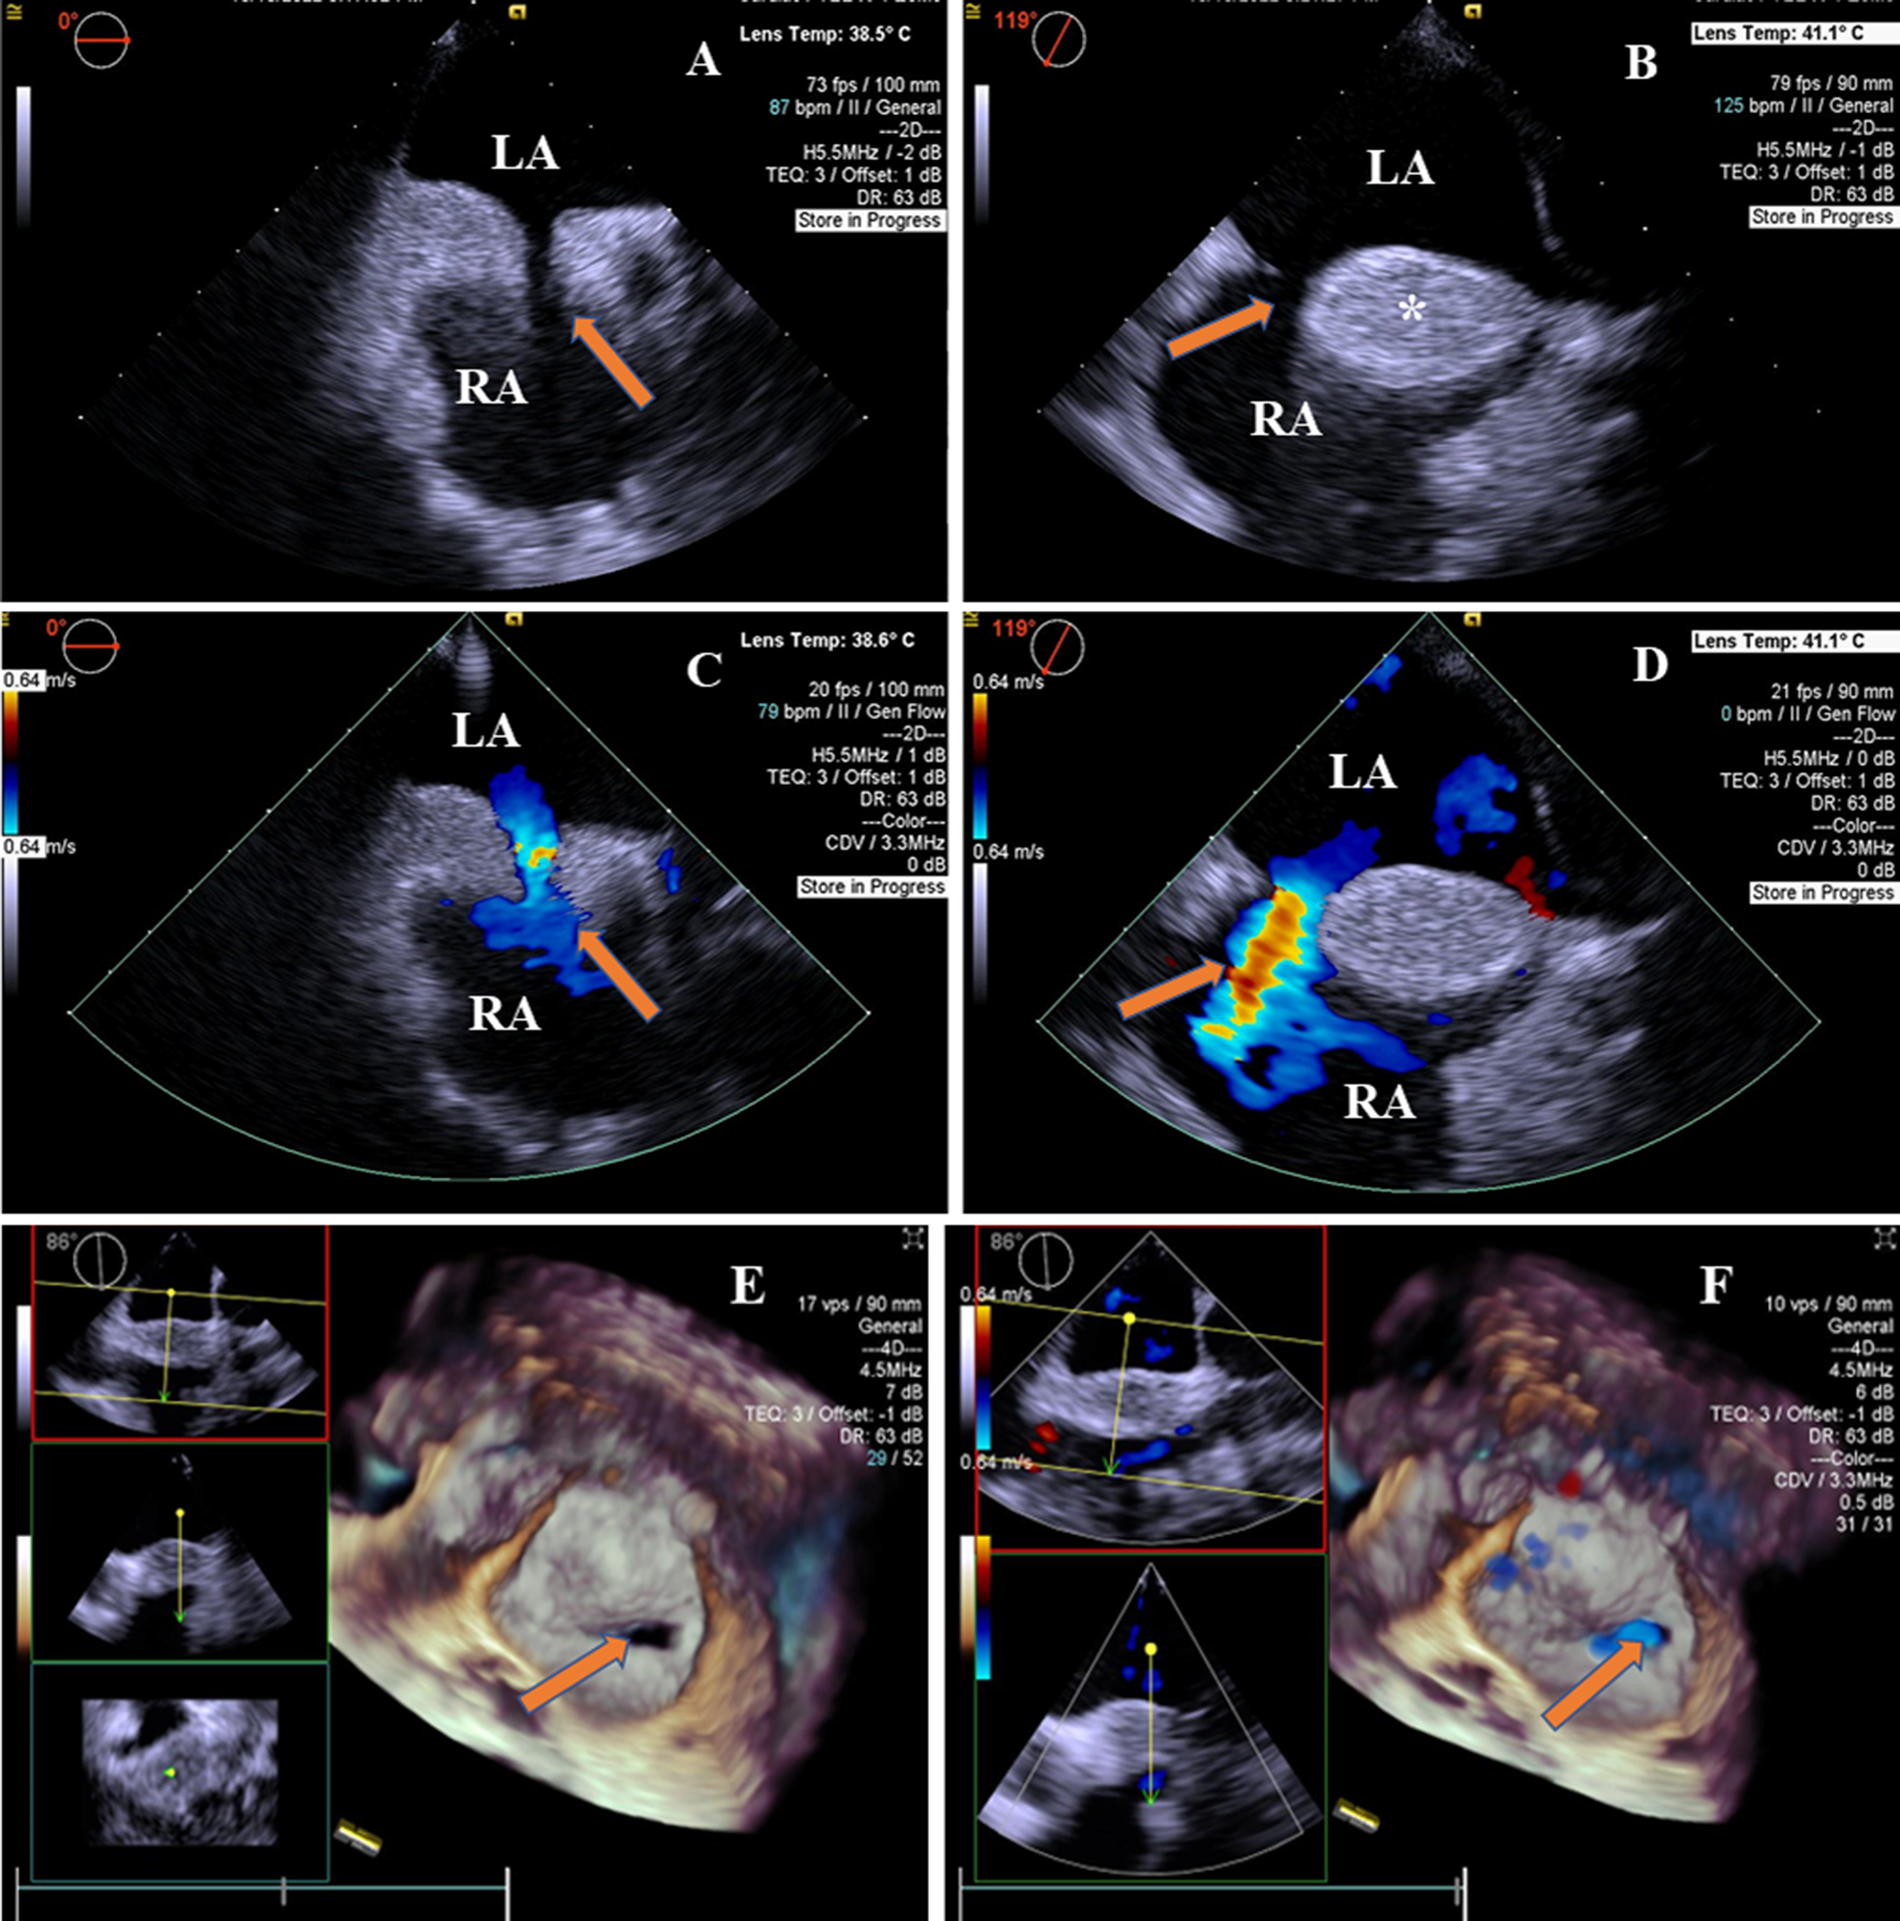

Two-dimensional transesophageal echocardiography revealed a “dumbbell”-shaped involvement of the cephalad and caudal regions with sparing of a single secundum ASD with a size of 9 mm × 13.2 mm. The maximal thickness of the interatrial septum was 20.7 mm, and the thinnest atrial septum was 1.6 mm from the view at 0°–180°. The atrial septum presented with a brightness feature, a rare condition characterized by the deposition of unencapsulated fat cells in this area (Figures 1A,B). There was no obstruction in the superior and inferior vena cava. A two-dimensional color Doppler ultrasound evidenced a left-to-right shunt through ASD (Figures 1C,D). The diagnosis of LASH with ASD was established based on the above findings. Real-time four-dimensional transesophageal echocardiography (RT4D-TEE) confirmed the lipomatous hypertrophy of the atrial septum and an oval-shaped ASD (Figure 1E and Supplementary Movie I). In addition, a color Doppler ultrasound of RT4D-TEE demonstrated the defect appeared foraminal in a location with a significant left-to-right shunt, suggesting a “foraminal” or “fossa” ASD (Figure 1F and Supplementary Movie II).

Figure 1

2D-TEE and 4D-TEE images revealed lipomatous hypertrophy of the atrial septum with atrial septal defect. (A) On 2D-TEE imaging, a single secundum ASD (arrow) and interatrial septum thickened to 20.7 mm in diameter were observed from 0° view. The septum with brightness features is characterized by the deposition of unencapsulated fat cells in the atrial septum. (B) 2D-TEE further documented a “dumbbell”-shaped involvement of the cephalad and caudal regions with sparing of the fossa ovalis (arrow) from 119° view. The interatrial septal fatty infiltration was demonstrated (*). (C) Color Doppler ultrasound of 2D-TEE showing a blood shunt from the left atrium to the right atrium (arrow) from 0° view. (D) Color Doppler ultrasound of 2D-TEE showing left-to-right shunt through ASD (arrow) from 119° view. (E) RT4D-TEE imaging reflected the whole ASD was surrounded by lipomatous hypertrophy of atrial septum (arrow) from 86° view. (F) Color Doppler ultrasound of RT4D-TEE showing blood flow of the ASD from the left to the right atrium (arrow). LA, left atrium; RA, right atrium.